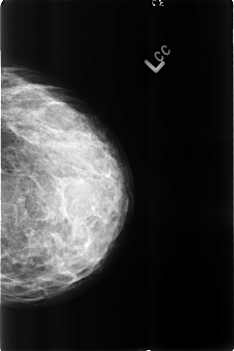

B_3191_1.LEFT_CC

LEFT_CC LINES 4560 PIXELS_PER_LINE 3040 BITS_PER_PIXEL 12 RESOLUTION 50 NON_OVERLAY